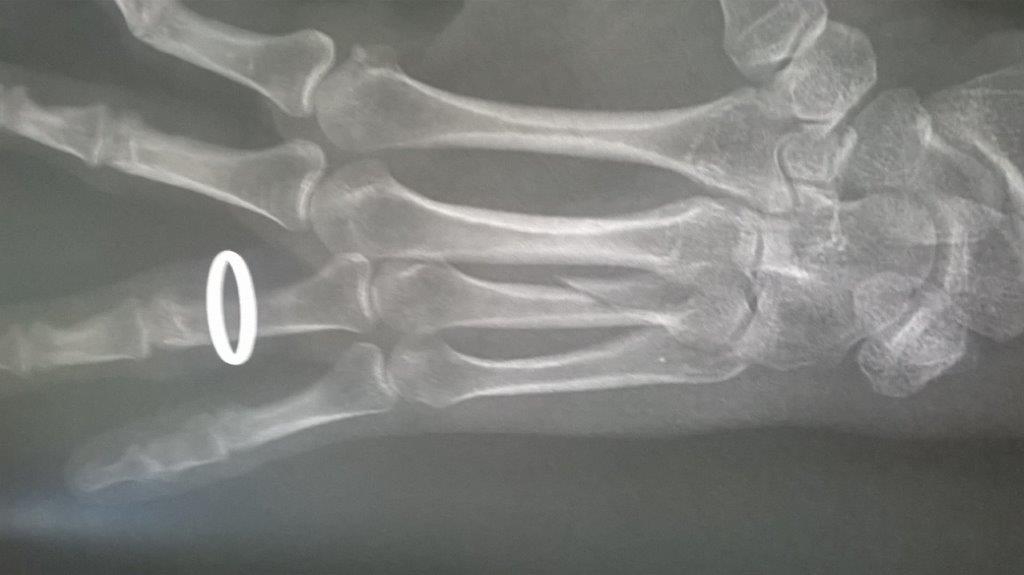

Résultat : fracture de la main gauche

Fichier(s) joint(s):

WP_20170914_001.jpg [ 47.5 Kio | Vu 29220 fois ]

Mais je confirme que ma saison de triathlon s'achève aujourd'hui. Main gauche immobilisé. Je suis au regret de déclarer forfait pour Paladru et d'abandonner les Mixirilliettes à leur triste sort